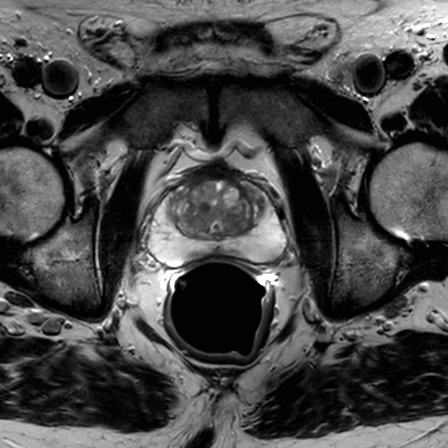

Prostate imaging with dS Endo + dS Torso coil

• Clinical Application